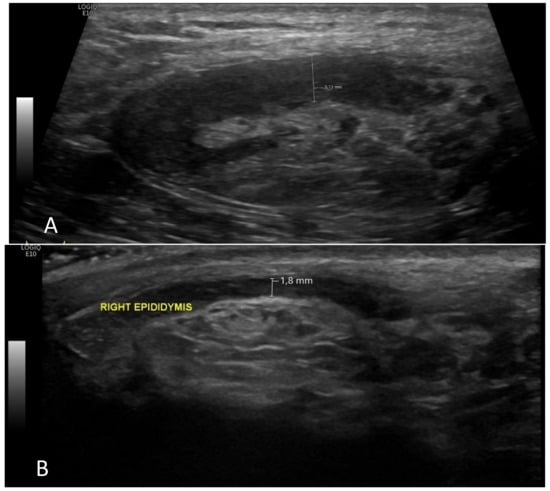

- A case of a patient with AIP type 1 and other organ involvement (bile ducts, testicles, nasal polyps, and lungs) is described.